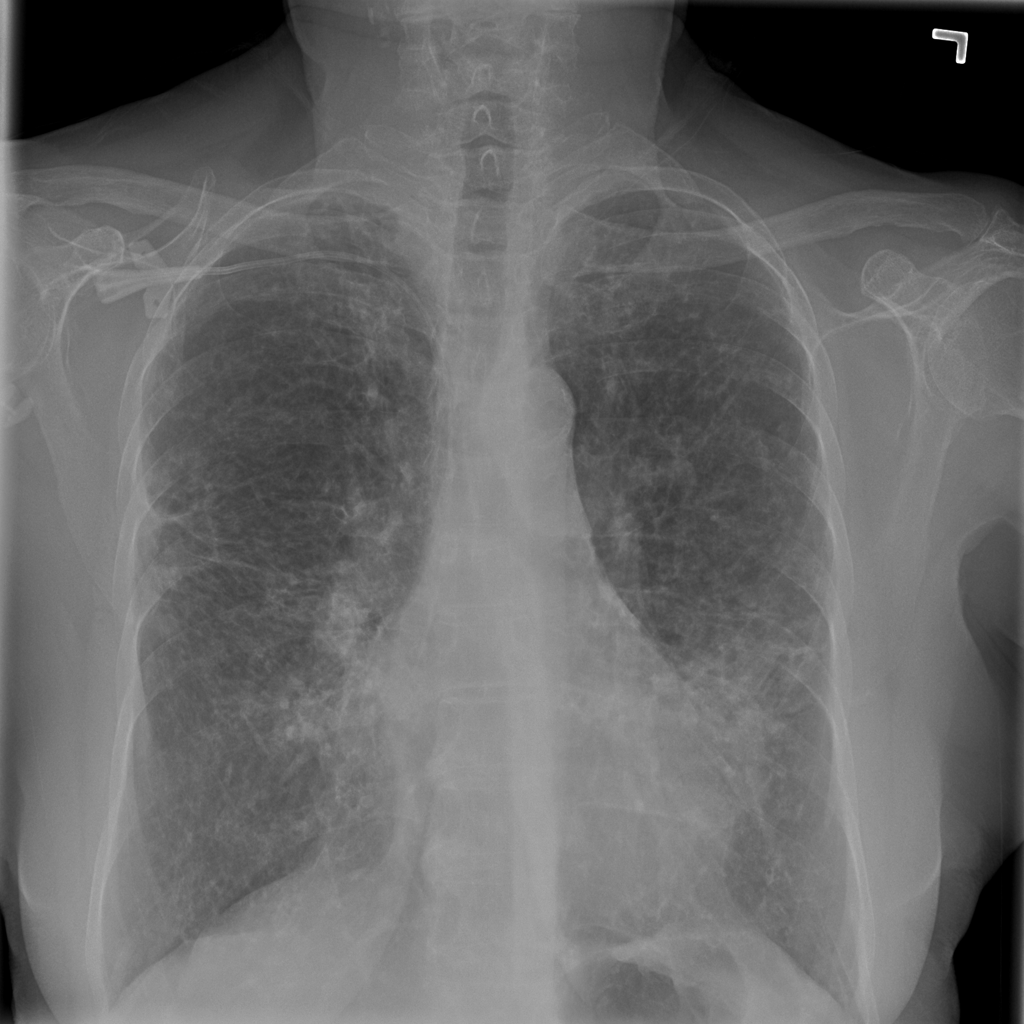

Consolidation

Consolidation refers to air-space filling that makes part of the lung appear denser on imaging.

Showing up to 90 reference images for Consolidation.

PAT-C1A7 · IMG-004Consolidation

PAT-C1A7 · IMG-004

PA